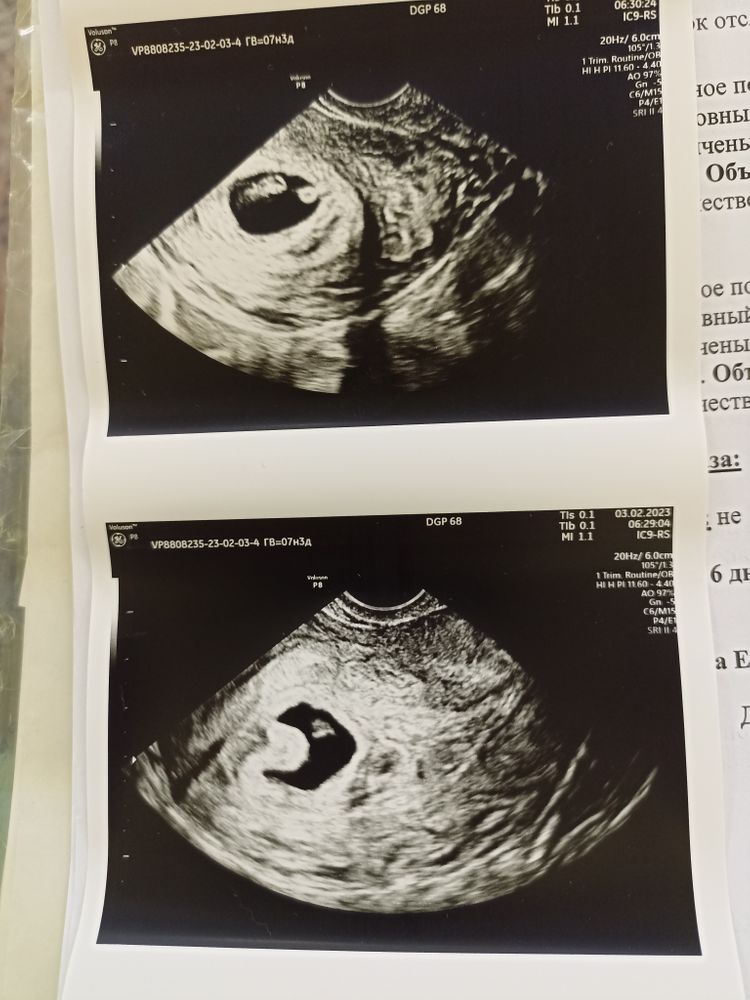

УЗИ на 7+4

УЗИ, КТГ, доплерУра, нашли сердцебиение!! 😍

Креветка растёт, гематомы нет 🥰 Какое-то странное образование в ПЯ, которое ребёнку не мешает, но узистка сказала, что никогда такого не видела и не знает, как это описать 😀 Решили обозвать гематомой в стадии организации - возможно, она была именно в этом месте. Сижу жду у кабинета врача, но как же сразу отпустило 🥰

Ходила на прошлой неделе в 6+3, не увидели сердцебиение и нашли гематому, отправили гулять неделю, а сегодня 7+4 акушерские и вот 😍